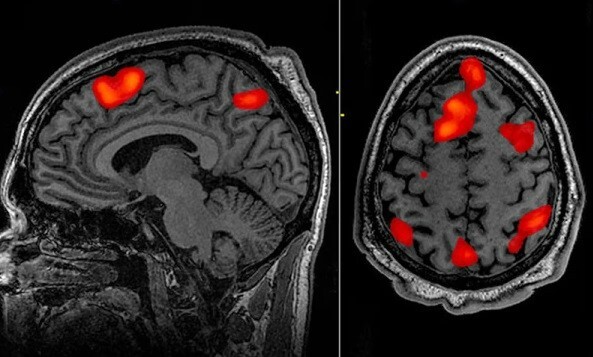

از سال ۲۰۱۹ گروهی از دانشمندان دانشگاه کلمبیا در کانادا به سرپرستی پژوهشگر ایرانی، نیما مسگرانی، با کمک هوشمصنوعی گامهای رو به جلویی را برای تحقق رویای امکان تبدیل افکار خاموش ذهن به گفتار برمیدارند. به اعتقاد این دانشوران، آنچه که اکنون گامهای نخستین خودش را میپیماید ظرف یکدهه آینده به واقعیتی دردسترس تبدیل خواهد شد. تیم نیما مسگرانی مشغول توسعه الگوریتمی است که بااستفاده از هوشمصنوعی و استفاده از دستگاه الکتروانسفالوگرام قادر است سیگنالهای مغز را به کلمات گفتاری تبدیل کند.

اما نیما مسگرانی، سرپرست گروه پژوهشگران دانشگاه کلمبیا در این تحقیقات بر ابزار خاصی بهنام «ووُکدر» بهمعنی «رمزگذار صوت» تکیه کرد. این دستگاه قادر است هر سیگنال صوتی را بهصورت کدهایی رمزگذاری کند. الگوریتمهایی با قابلیت یادگیری جملات و داستانهای کوتاه و بازتولید کلمات و گفتارهای خاص در این دستگاه نصب شدهاند. این همان فناوری است که به سامانه دستیار صوتی الکسا محصول آمازون و سیری محصول اپل اجازه میدهد که به سوالهای کاربران پاسخ صحیح ارائه دهند. این مطالعه دادههایی را از پنج بیمار مبتلا به صرع درحالیکه تحت جراحی مغز و اعصاب بودند جمعآوری کرد. در مغز این بیماران یک سری الکترود کاشته شده بود که به دانشوران اجازه داد همانطورکه بیماران به داستانهایی که چهار نفر مختلف تعریف میکردند گوش میدادند اندازهگیریهای الکتروکورتیکوگرافی جامعی انجام دهند. هر ضبط عصبی حداکثر ۳۰ دقیقه طول کشید.

پساز جمعآوری دادهها، دستگاه رمزگذار صوتی امواج مغزی تولیدشده در قشر شنوایی را خواند و از آنها برای تبدیل آنچه که مغز شنیده بود به گفتار استفاده کرد. سپس صدای تولیدشده با سامانه هوشمصنوعی از هرگونه اصوات مزاحم پاک و درنهایت، دادهها برای شنوندگانی بیرون از این آزمایش پخش شد. بهگفته نیما مسگرانی، شنوندگان تا 75 درصد مواقع توانستند صداها را بفهمند و تکرار کنند که در مقایسه با تلاشهای قبلی بهطور متوسط بینظیر است. او همچنین پیشبینی میکند که این فناوری دستکم تا یک دهه آینده در سطح جهانی در دسترس خواهد بود و هرچند امکان انجام اندازهگیریهای الکتروکورتیکوگرافی (در تماس مستقیم با کورتکس مغز) محدود است، اما بههررو، این آزمایش میتواند پایه و اساس تبدیل افکار انسان به گفتار باشد. گام بعدی، اصلاح الگوریتمها است تا بتوانند کلمات و جملات پیچیده را رمزگشایی کنند، تاحدیکه این فناوری در آینده، واقعا بتواند به نقطه عطفی تبدیل شود که نهفقط در زندگی روزمره، که برای رفاه بیمارانی که بهدلیل بیماریهای تخریب نورونی و آسیبهای مغزی نمیتوانند صحبت کنند هم مفید باشد.

پساز مطالعات سال ۲۰۱۹ دانشمندان دانشگاه کلمبیا، گروهی از پژوهشگران دانشگاه کالیفرنیا در سال ۲۰۲۰ الگوریتمی را توسعه دادند که قادر است امواج مغزی را پردازش و آنها را به جملات معنادار تبدیل کند. براساس دادههای این محققان که در نشریه تخصصی نیچر نوروساینس منتشر شده است، میانگین میزان خطای این مدل برابر با ۳ درصد است. جوزف ماکین، متخصص یادگیری ماشین در این پژوهش میگوید: «واسطهای ذهن و ماشین موفقیت محدودی در رمزگذاری فعالیتهای عصبی نشان میدهند و قادر به رمزگشایی قطعات کلمات یا جملات خاص ساده هستند.» کار ماکین و گروهش با مشارکت چهار داوطلب شروع شد که در مغز آنها هم الکترودهایی برای نظارت بر تشنجهای صرع کاشته شده بود. از داوطلبان خواسته شد تا حدود ۵۰ جمله مختلف را چندبار با صدای بلند بخوانند: جملات سادهای چون «تینا ترنر یک خواننده پاپ است» یا «آن دزدها ۳۰ جواهر را دزدیدند» و همزمان دانشمندان فعالیت مغز آنها را ثبت کردند. سپس الگوریتم هوشمصنوعی که برای تبدیل سیگنالهای مغز به نمایشهای انتزاعی، در قالب رشتههای عددی طراحی شده بود، این دادههای جمعآوریشده را پردازش کرد.